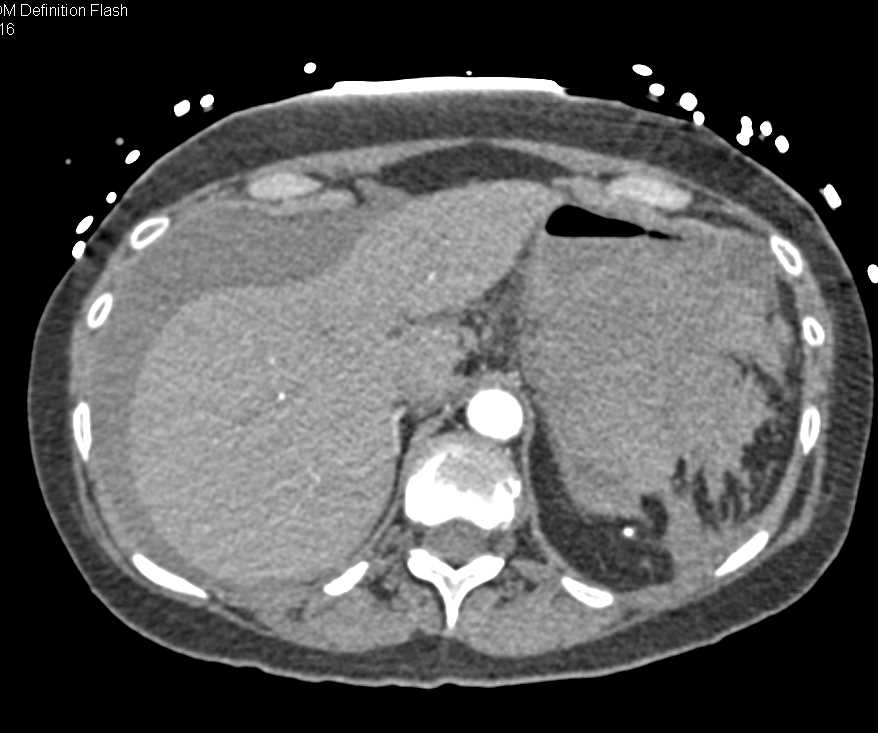

Hemoperitoneum due to Hepatic Bleed, in a Patient with Hx of Renal Osteodystrophy